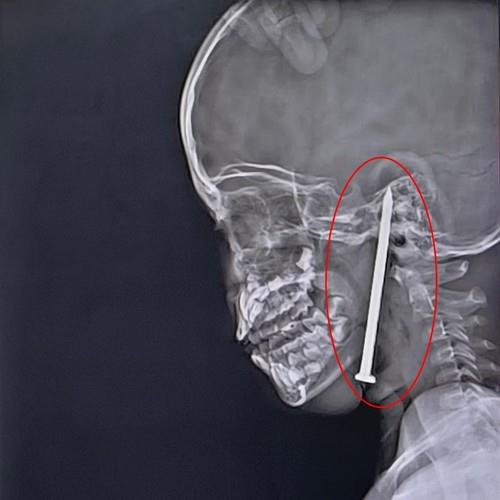

Dečaku se tokom igranja ekser od 8 cm zabio u glavu: Lekari se smrznuli kad su videli snimak, ono što je potom usledilo je čudo (FOTO)

dečak ekser profimedia-1005203967.jpg

4 / 4

TIM / Jam Press / Profimedia